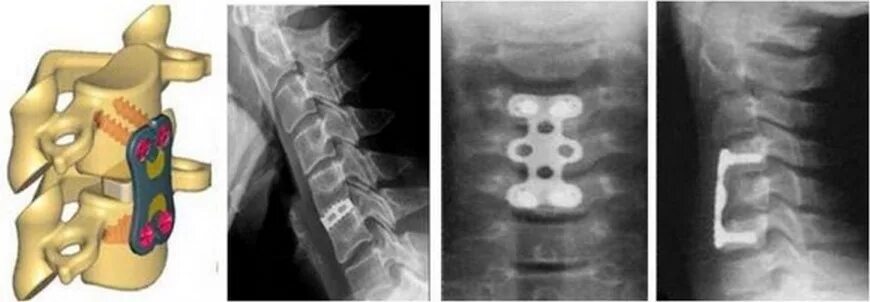

Операция по удалению грыжи шейного отдела